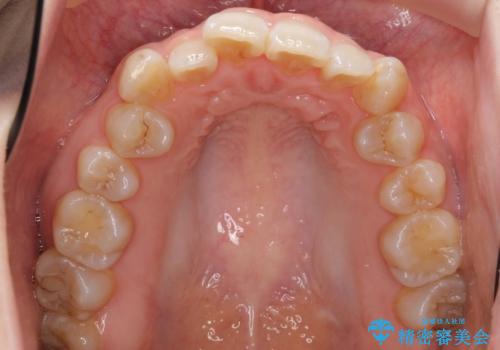

ハーフリンガル 犬歯のねじれ 歯根の外部吸収している歯を抜歯

- 前歯のねじれを主訴に来院。

レントゲンを撮影したところ、右下4は神経のない歯で、外部吸収といって、根がだんだん短くなり、やがて抜けてしまう症状になっていました。また、アンキローシスを起こしている可能性があるため、動かない可能性が高い状態でした。

上顎前歯も唇側傾斜しておらず、もともと叢生が多くない状態で上下左右を抜歯した上、リンガルで治療を行なったため、多少治療期間がかかりました。